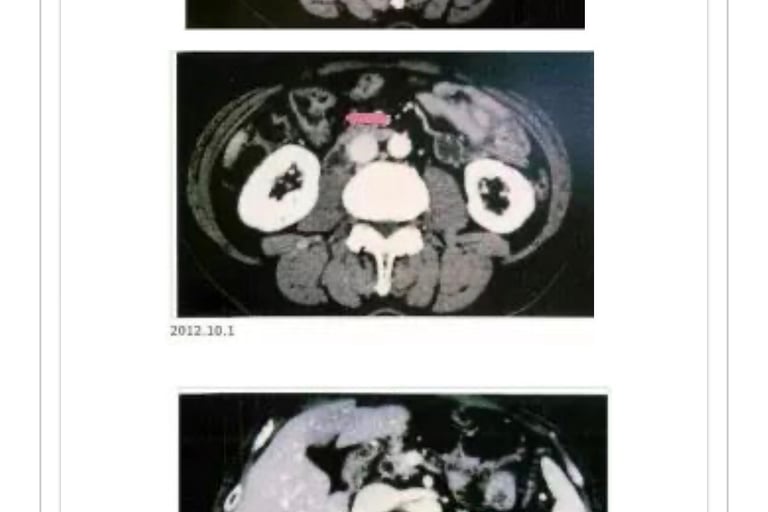

(肿瘤标记)T・M(1936年生、男性)2005年2月、患者打嗝不止就医未发现异常。

来我院就医,诊断发现横膈膜左侧附近有肾癌共振反应,去大医院复检结果左肾上有11×10×9cm巨大肿瘤。

05年4月4日手术摘除。术后发现左肺2个和右上叶较小转移(照片1)。

2005年4月20日来院接受MW治疗,至6月20日合计照射16次。3个转移肿瘤2个消失。2005年5月11日追加NK・T细胞免疫疗法(每隔2周共计6次)。患者恢复状态较好。3个月复检一次。

2009年1月肺癌反应出现后MW照射消失。

1月27日胸部CT成像显示左肺下叶阴影较大(照片2),患者对干扰素副作用反应明显使用终止。

对左下叶的肿瘤标记建议摘除,由于患者并无癌症共振反应所以未进行手术。12年11月至今,患者除了肌酸酐值偏高外其他指标正常。